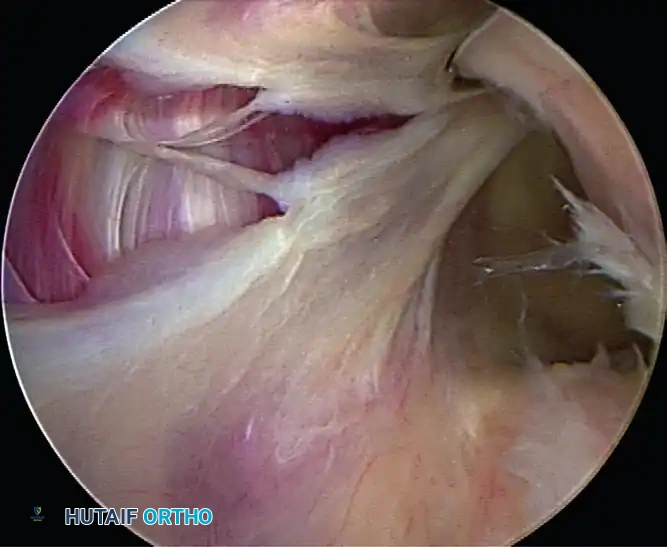

4. Suture Passing and Superior Advancement

To eliminate the drive-through sign and restore physiological tension, the capsule must be shifted superiorly and laterally.

- Retrieve the most inferior suture limb out of the posteroinferior cannula using a suture grasper.

- Use a Spectrum suture passer through the anterior cannula to take a substantial (1 cm) bite of the capsule and labrum inferior to the anchor site.

C, A 1-cm capsular bite taken with Spectrum suture passed distal to anchor.

- Shuttle the PDS relay suture out the posterior cannula, load the anchor suture, and pull it through the capsulolabral tissue.

- Retrieve the corresponding suture limb and tie a secure, low-profile sliding knot (e.g., SMC or Weston knot) backed up by alternating half-hitches.

5. Recreating the Anterior Bumper

Proceed superiorly, placing the second and third double-loaded anchors. Firmly secure the sutures, compressing the capsuloligamentous complex to the abraded bone surface. This "loop and knot fixation" rolls the tissue up onto the glenoid face, recreating a robust anterior soft-tissue bumper.

D, Knots tied re-creating soft tissue bumper.

B, Restored anterior labral bumper (arthroscopic view).

C, Restored anterior labral bumper (alternate angle).